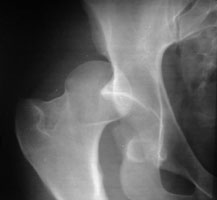

The majority of hip dislocations are posterior and due to impaction of the femoral head upon the acetabulum from direct force to the distal femur (generally against a dashboard). This usually results in fracture of the posterior rim of the acetabulum and may result in sciatic nerve injury. With anterior dislocation, the femoral head is displaced into the obturator or pubic region. With internal dislocation, the femoral head projects into the pelvic cavity.

- Click on the image for a larger versionAAP radiograph of the right hip. There is posterior dislocation of the femoral head.